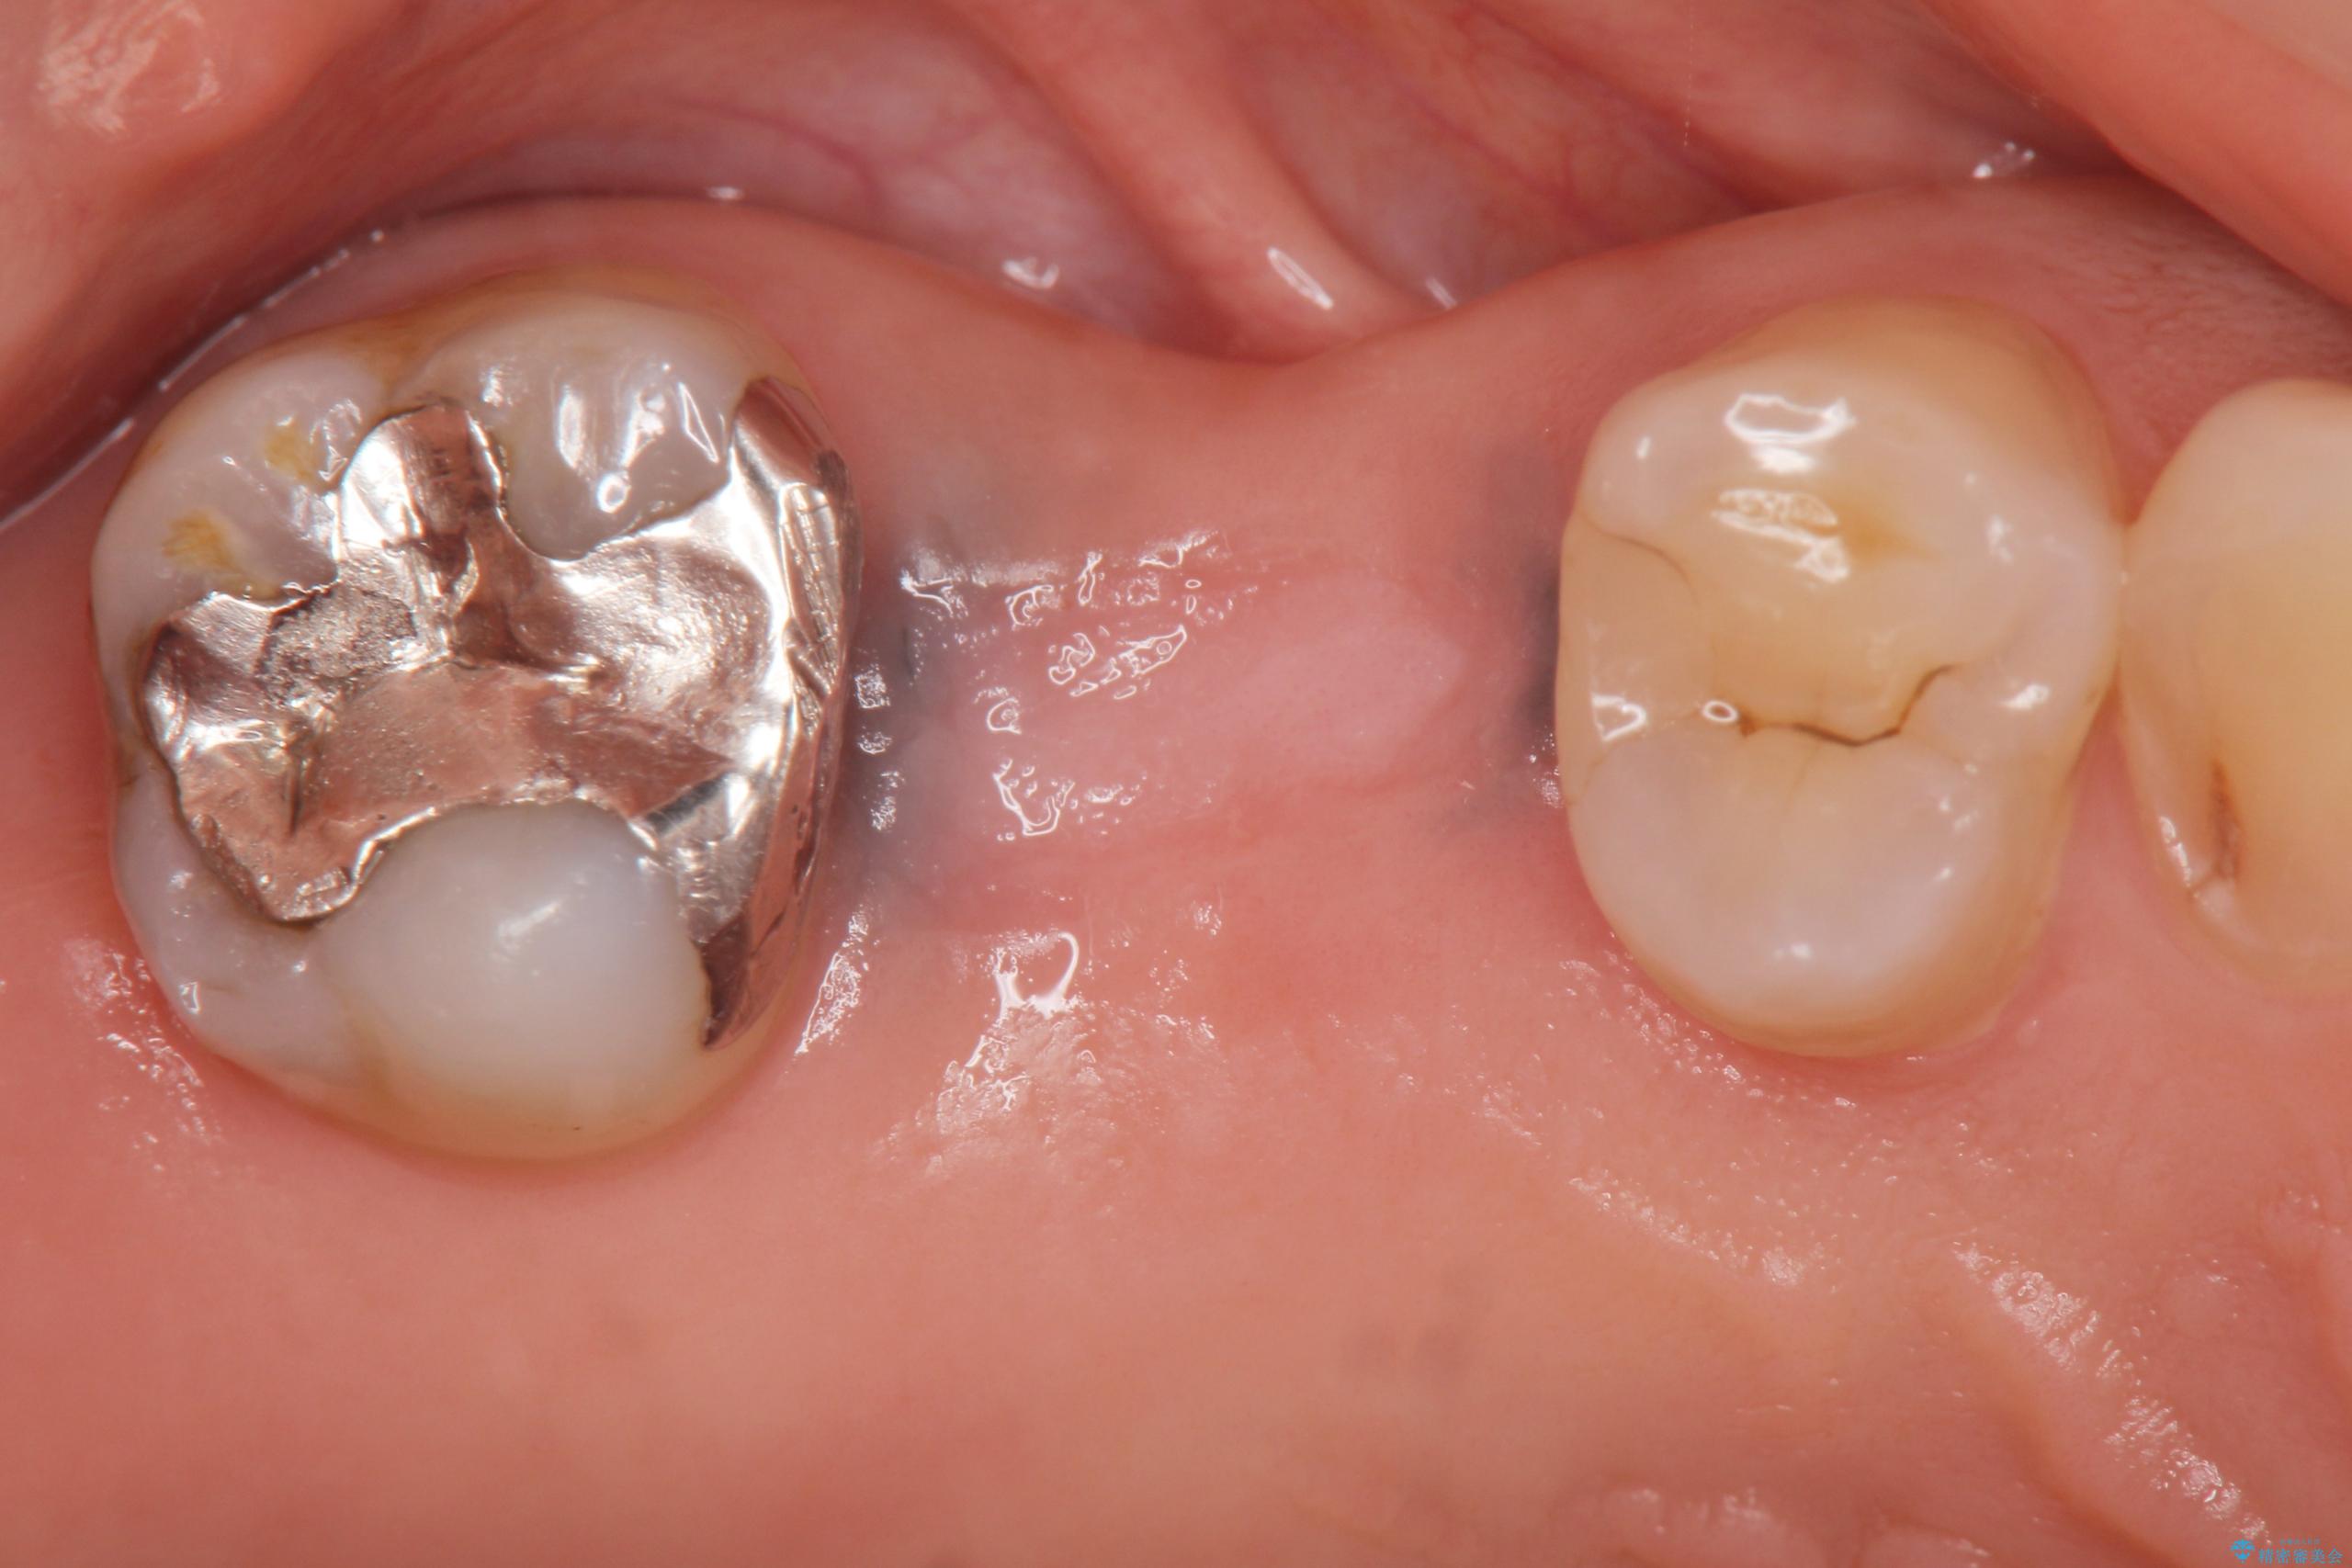

インプラント治療を行ったことで前後の歯を削らずに咬合機能の回復をすることができ、大変ご満足いただけました。

44万円(インプラント・チタンカスタムアバットメント・ジルコニアクラウン・仮歯)